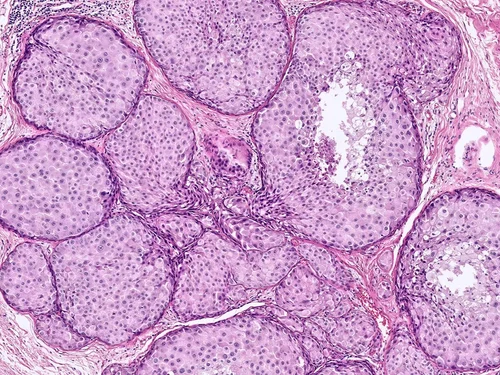

Normal Breast Tissue, Lobule

The mammary ductal-lobular system in lined by a dual cell population comprised of an inner epithelial cell layer and an outer myoepithelial cell layer. Myoepithelial cells can vary in appearance, including prominent cytoplasmic clearing and myoid features.